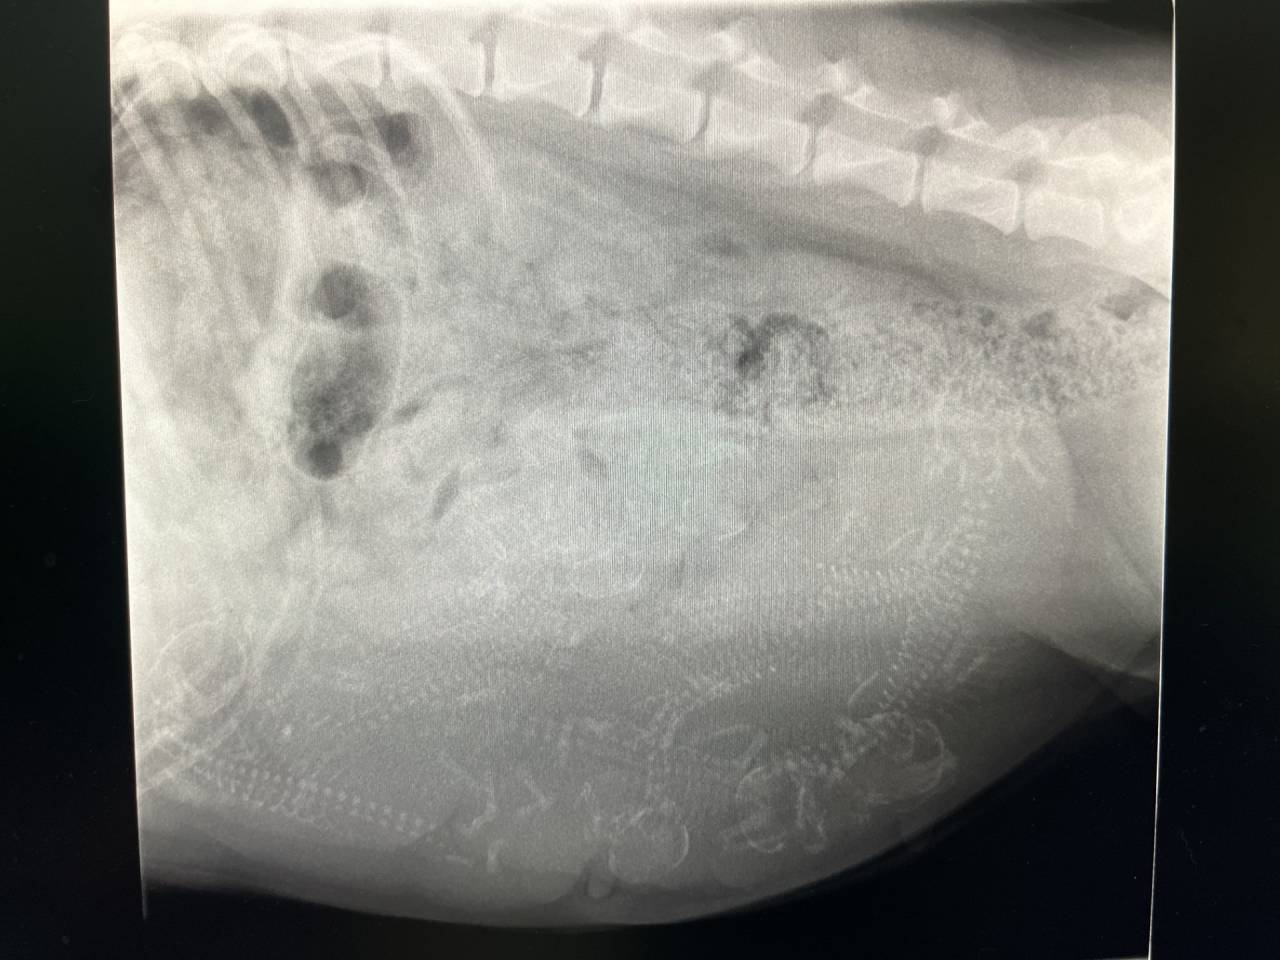

エルちゃん、バッチリ!!8~9匹+アルファ・・・

股関節も凄く良いし、あとは、エルちゃんの体力次第ですね。頑張れ!!!